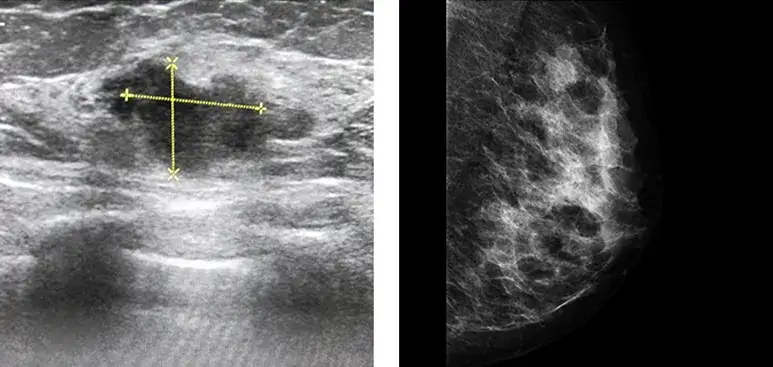

Zmiana hipoechogeniczna w piersi co to znaczy? Jest to termin używany w diagnostyce ultrasonograficznej, który odnosi się do obszarów w tkance piersi, prezentujących ciemniejszy obraz niż otaczające je tkanki. Taki wynik może budzić obawy, ale w wielu przypadkach nie oznacza on od razu problemu zdrowotnego. Kluczowe jest zrozumienie, co taka zmiana oznacza oraz jakie są jej implikacje.

Obecność zmian hipoechogenicznych w piersiach jest wynikiem mniejszych odbić fal ultradźwiękowych. Te zmiany mogą być spowodowane różnymi czynnikami, takimi jak torbiele w piersiach, które są zwykle łagodnymi i wypełnionymi płynem strukturami. Inne przyczyny to guzy piersi, które mogą być zarówno łagodne, jak gruczolakowłókniaki, jak i złośliwe, jak rak piersi.

Diagnostyka zmian hipoechogenicznych opiera się głównie na badaniach ultrasonograficznych (USG), które pozwalają zidentyfikować charakter zmian. W przypadku wykrycia takiej zmiany, kluczowe jest zlecenie dalszych badań, w tym biopsji, aby dokładnie określić, czy zmiana jest łagodna czy złośliwa. Rezonans magnetyczny piersi również może pomóc w ocenie stanu tkanek, a badania genetyczne mogą być wskazane w przypadku rodzinnych historii nowotworów.